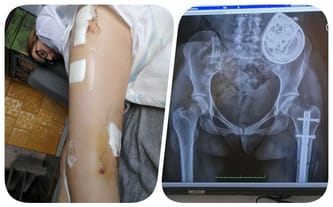

Klaudia do chwili obecnej przeszła dwie operacje, dzięki którym może w ogóle chodzić. Każdy jej krok jest ogromnym sukcesem, okupionym litrami potu, bólu i determinacji. Córka dostała się do liceum, chce spełniać swoje marzenia. Ja jako matka marzę tylko o jednym - żeby nie musiała znaleźć się na wózku. Do tego jednak potrzebna była kolejna bardzo skomplikowana operacja...

Dzisiaj, będąc już kilka miesięcy po operacji, musimy cały czas walczyć, żeby jej efekty nie zostały zmarnowane. Żeby niesprawne do tej pory nogi miały szansę służyć Klaudii tak, jak do tego zostały stworzone. Wyjazdy na rehabilitację do Warszawy wiążą się jednak z ogromnymi wydatkami, dlatego raz jeszcze ośmielamy się Was prosić o pomoc.